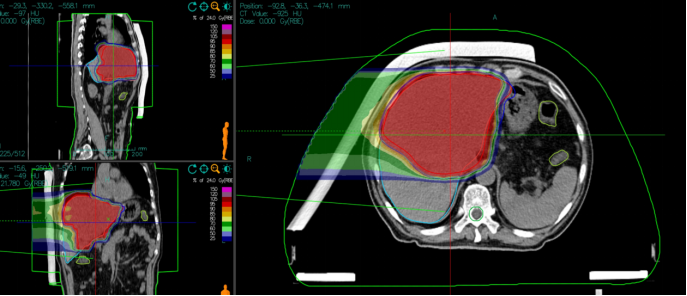

Carbon Ion Radiotherapy: Beam Direction and Dose Distribution

First Course Plan:

Patient Position: Supine position.

Lesion Characteristics: Diffuse lesions within the liver parenchyma, delineated using 4D-CT (four-dimensional computed tomography) with multiple respiratory phases to account for tumor motion.

Target Volumes:

Liver-PTV (Planning Target Volume): Approximately 606 mL.

PTVboost: 32 Gy(RBE)/8 fractions (fx), followed by 4 Gy(RBE)/fx